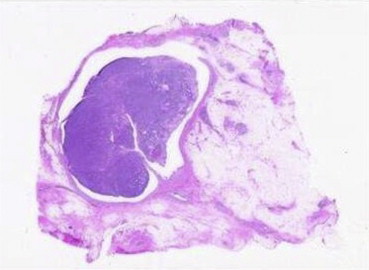

A 44-year-old woman was referred to our hospital with nipple discharge from her left breast. Mammography showed the mass shadow and dilated mammary duct. Ultrasonography revealed a solid tumor beneath the left areola that was 17 mm in diameter, with a dilated mammary duct (Fig.1). Contrast-enhanced magnetic resonance imaging (MRI) showed an early-enhanced and wash-out pattern of the tumor, in addition to the dilated mammary duct. Fine needle aspiration cytology was performed; the findings of which were insufficient to exclude malignancies of the breast. We planned to perform a duct-lobular segment ectomy using near-infrared ICG-fluorescence imaging intraoperatively. Under general anesthesia, a silicone tube intended for the treatment of lacrimal passage obstruction (N-S tube; Kaneka Medicus, Osaka, Japan) was inserted into an orifice of a fluid-discharging mammary duct, and 1 mL dye-fluorescence liquid comprising 0.025 mg/mLICG (Diagnogreen; Daiichi Pharmaceutical, Tokyo Japan) with 0.02 mg/mL indigocarmine (Daiichi Pharmaceutical) was injected into the mammary duct.

Ultrasonography revealed a solid tumor beneath the left areola with a dilated ...

Figure 1.

Ultrasonography revealed a solid tumor beneath the left areola with a dilated mammary duct.